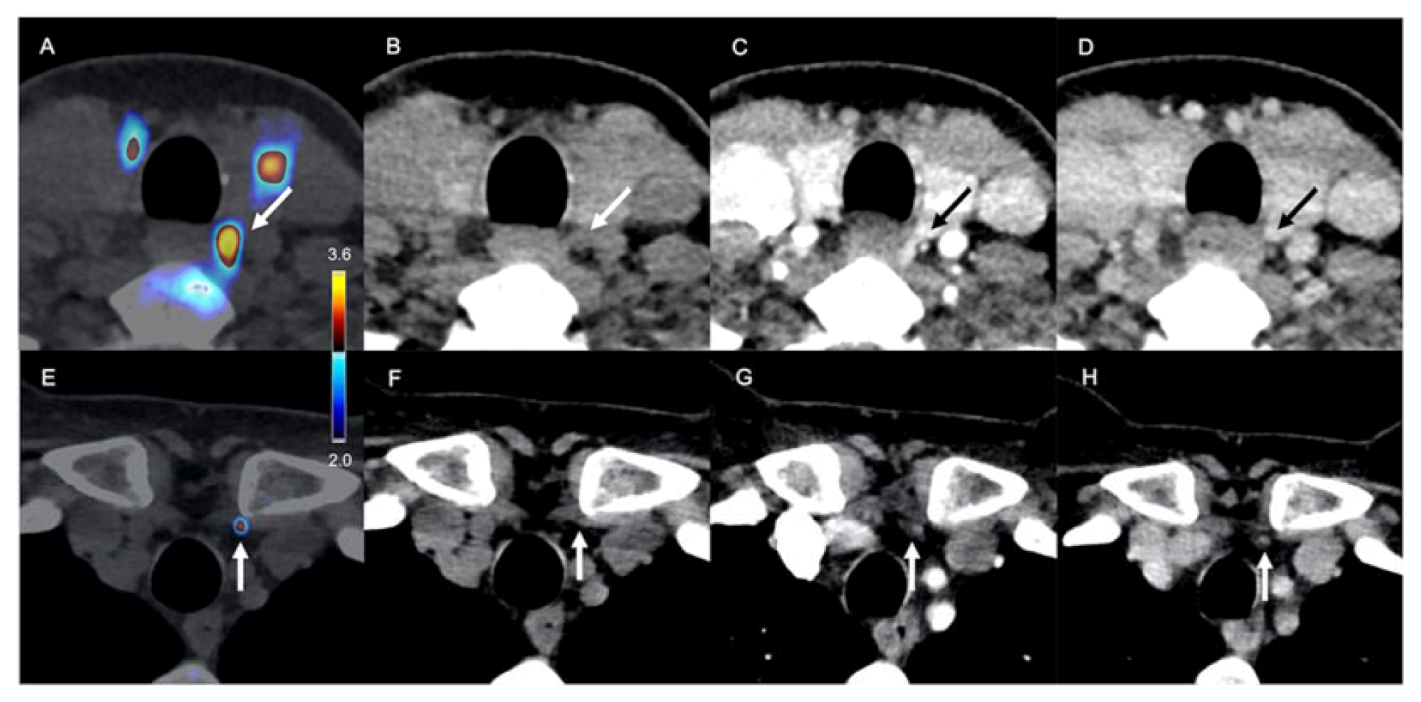

- Pretet, V.; Rotania, M.; Helali, M.; Ignat, M.; Vix, M.; Imperiale, A. 18F-Fluorocholine PET and Multiphase CT Integrated in Dual Modality PET/4D-CT for Preoperative Evaluation of Primary Hyperparathyroidism. J. Clin. Med. 2020, 9, 2005. [Google Scholar] [CrossRef] [PubMed]